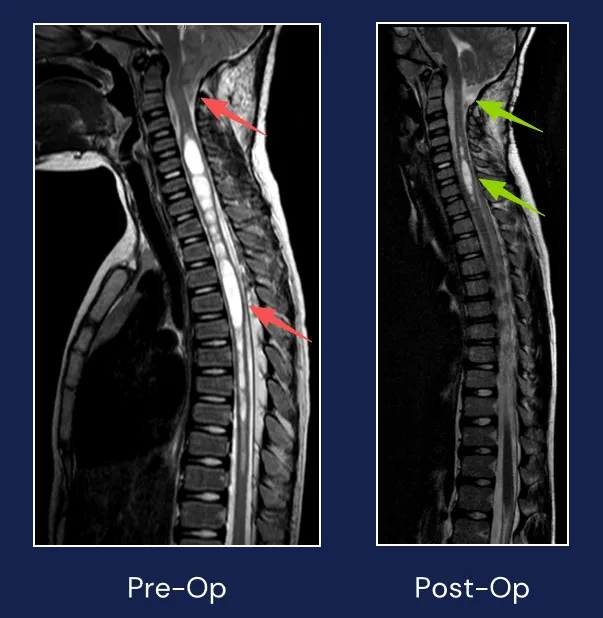

初期检查仅发现玮玮患有轻度脊柱侧弯,但当获悉患儿还存在共济失调症状时,医生立即建议转诊神经外科进行详细影像学检查。由此,玮玮被确诊患有小脑扁桃体下疝畸形(CM,又称Chiari畸形),并伴有脊髓空洞症。

实际上,对于症状明显或症状进展的小脑扁桃体下疝合并脊髓空洞症患者,通常建议手术治疗。手术关键在于去除脊髓空洞症的病因(小脑扁桃体下疝畸形),减轻小脑疝引起的压力增高,恢复脑脊液循环。一旦病因解除,脊髓内空洞将逐渐缩小,从而达到治疗效果。因此通常无需处理空洞本身。

术后脊髓空洞显著改善

数日后,手术按计划进行。在Rutka(鲁特卡)教授主刀下,手术过程十分顺利。小脑扁桃体下疝畸形成功去除后,玮玮的脊髓空洞明显缩小。